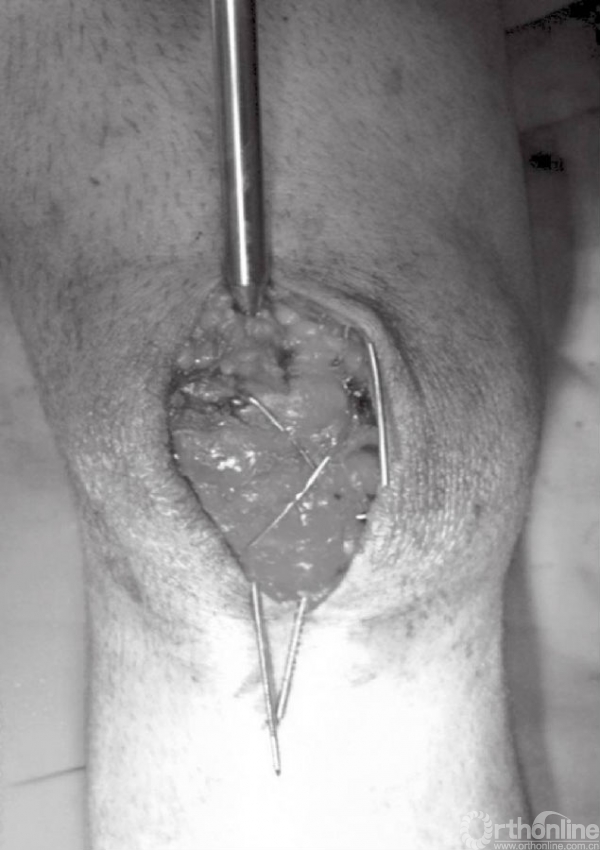

骨折端固定可采用1.6mm克氏针或者4.0mm空心螺钉。可在髌骨的中心部位,离髌骨前侧5~8mm处拧入2根克氏针或者2枚空心螺钉。也可采用克氏针以倒打的方式先穿过近端骨折块,在复位后再穿过远端骨折块(图7~10)。

图7 A~C以逆行打入的方式在骨折近端置入克氏针,离髌骨前侧约5mm

图8 置入的两枚的克氏针应保持平行,位置约为髌骨的大致1/3及2/3位置

图9 在复位钳的帮助下完成髌骨骨折复位以及临时固定

图10 在临时固定的同时,将克氏针穿过远端骨折块